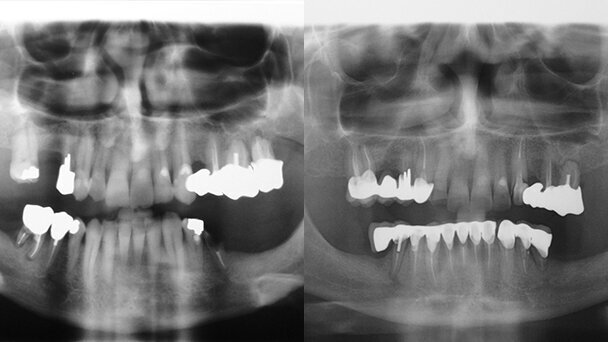

Nell'elaborato del CTU nominato dal Giudice, si legge, tra le altre cose: è presente a destra una protesi di quattro elementi in metallo ceramica dal 13 al 16; 23 è ridotto a residuo radicolare, con perdita del perno e della ricostruzione in resina composita; usura dello smalto palatino di 11-12-21-22; l'esame RX rivela esiti di terapie endodontiche su 13-14-16-23-25-26. All'arcata inferiore mancano gli elementi 36-37-38-45-46-47-48; 44 è privo di corona, ridotto a residuo radicolare; è presente protesi fissa in metal ceramica di otto elementi, dal 35 al 43 fratturata in due tronconi tra il 32 e 33 con esiti di limature distali da verosimile taglio di elementi protesici; gengivite ipertrofica in corrispondenza di 31 e 42; l'esame RX rivela esiti di terapie endodontiche su tutti gli elementi residui e presenza di zona di osteolisi periapicale del 43.

Si trattò di inadempienza contrattuale per cui fu prevista la restituzione di quanto pagato in merito alla protesi inferiore. Inoltre, a causa dei trattamenti incongrui, derivarono lesioni con conseguente perdita di 45, di 44 e 23 che richiesero successiva estrazione ed emenda con terapia implantoprotesica. L'inadeguato trattamento endodontico e ricostruzione coronale, evidenziabili nelle Rx prodotte, portarono alla perdita dell'elemento.

Per quanto riguarda l'usura progressiva degli incisivi superiori, maggiore di quella fisiologica attendibile, come documentato tra il confronto delle RX pre e post cure, si ritenne che la maggior usura fosse da emendare con una protesizzazione di tali elementi in ceramica. Venne riconosciuto un danno biologico permanente residuo dopo l'emenda dell'1-1,5% e una Invalidità Temporanea Biologica di 20 giorni, dei quali 5 a parziale massima (50%) e 15 a parziale minima (25%).